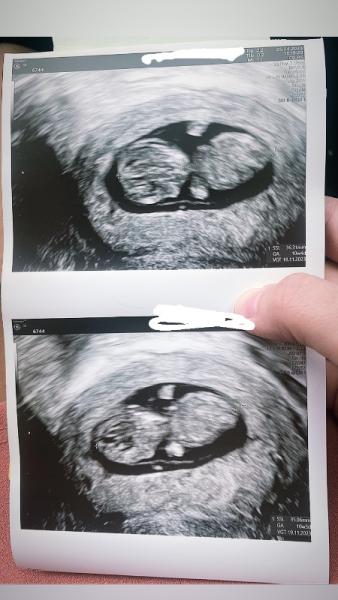

Hi ihr Lieben, komme vom Termin alles wie es sein sollte! Ein Foto haben wir auch bekommen und wurden vordatiert 10+4 statt 9+3 wie es lt. dem 1. US gewesen wär. Auch wenn ein Terminchaos herrscht hab ich jetzt beschlossen ich nehm den neuen Termin bis zum CT hin. Es beruhigt mich unheimlich, dass ich das Herzchen heute wieder gesehen habe. Es hat uns sogar kurz gewunken

Foto ist nicht mitgegangen.

Bild zu